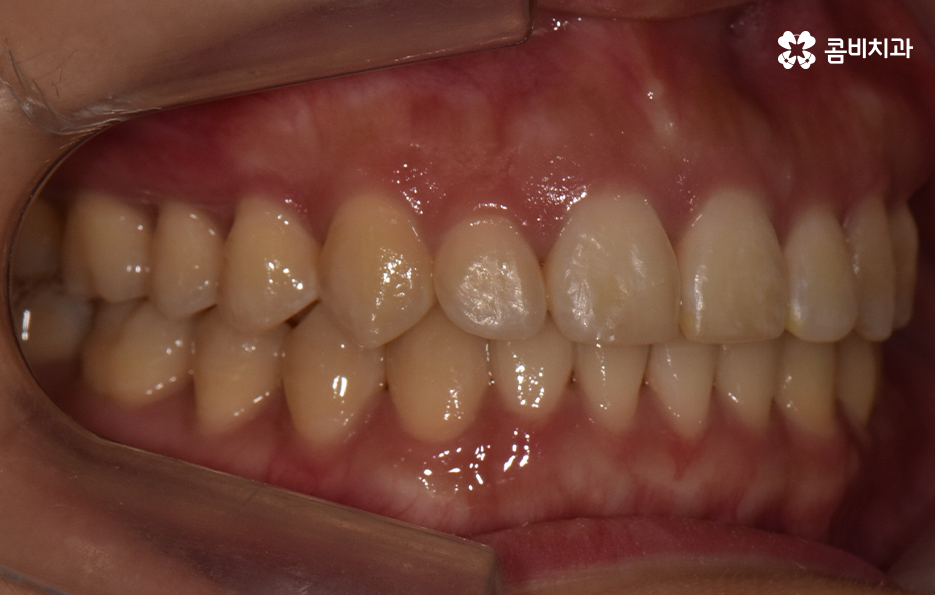

그렇기 때문에 비발치치아교정이 좋다고 생각하기 보다는 개인에 따라서는 치아의 이동 공간 확보를 충분히 하기 위해 발치가 필요한 경우도 있고 얼굴 변화나 부정교합의 개선을 위해 발치가 필수적인 경우도 있을 거예요

반면에 비발치치아교정으로도 충분히 좋은 결과를 얻을 수 있는 경우도 있을텐데 이러한 치료 과정 상의 특징과 장단점을 고려하여 자신의 치료 계획을 경험 많고 숙련된 교정 전문의와 잘 상의하실 필요가 있어요

단순히 비발치치아교정이 발치를 안해도 되니 무조건 좋다고 판단하기 보다는 각 개인의 치료 목적과 구강 및 골격, 얼굴형의 상태를 종합적으로 정밀 검진하여 자신에게 적합한 치료 계획을 잘 세우는 것이 중요하다고 강조드리고 있어요